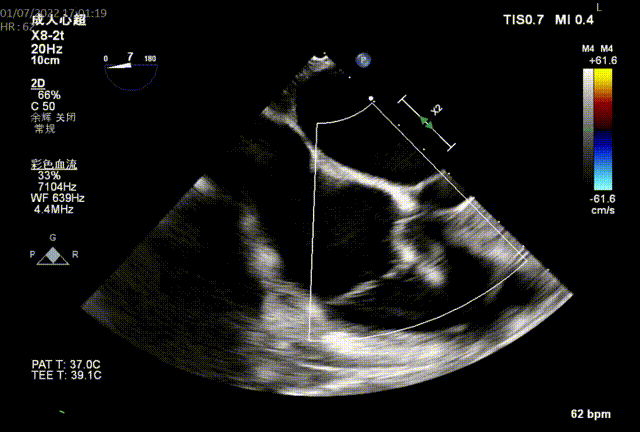

图2:术中TEE

同时其夹子系统继承于申淇淇麟®-经导管二尖瓣夹及可操控导引导管系统优秀设计,具备四个不同型号的夹子及瓣叶分开捕获能力,从而适用于更加复杂多变的三尖瓣解剖。因该患者三尖瓣反流束较宽,瓣叶存在较宽的关闭裂隙,术中很好的利用了瓣叶分开捕获的功能,于前隔瓣区域行瓣膜缘对缘修复。植入一枚长宽夹子后,术后即刻患者反流减至轻度。患者术后恢复良好,出院前TTE提示三尖瓣轻度反流。